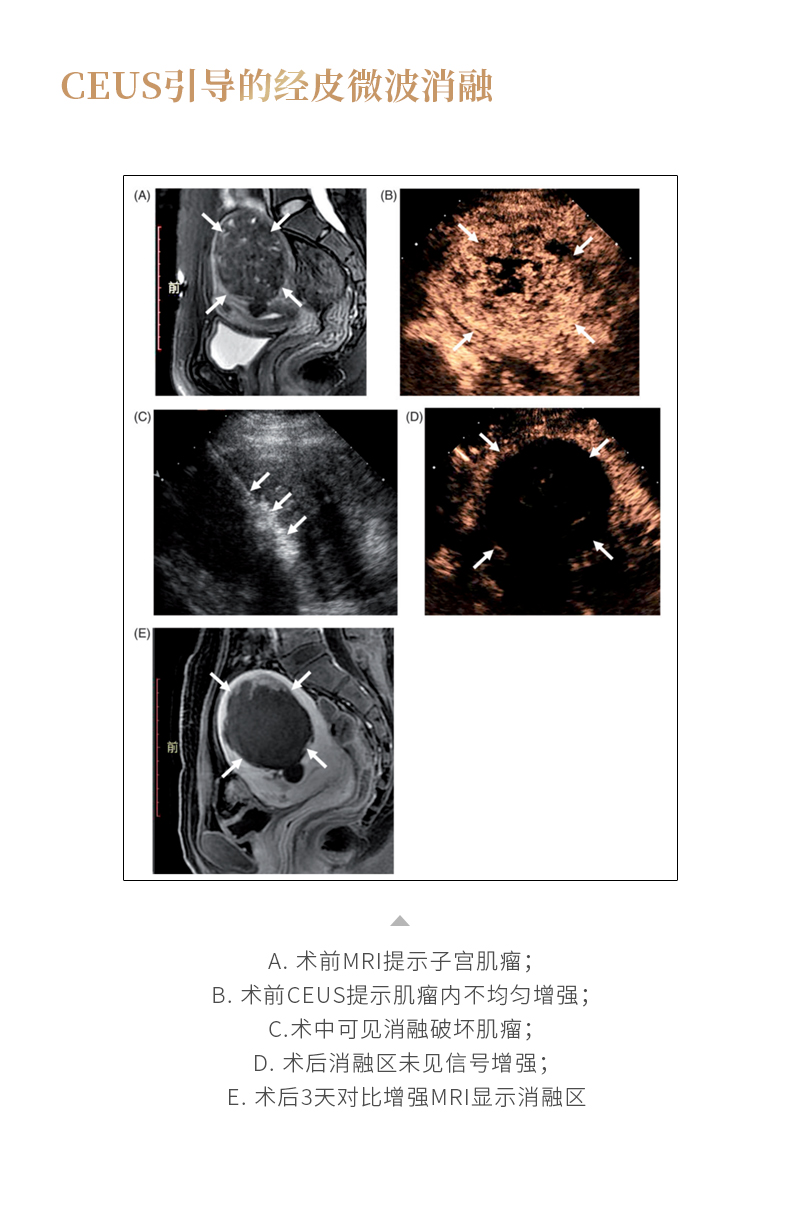

消融治療子宮肌瘤——【海杰亞科研資訊】第260期